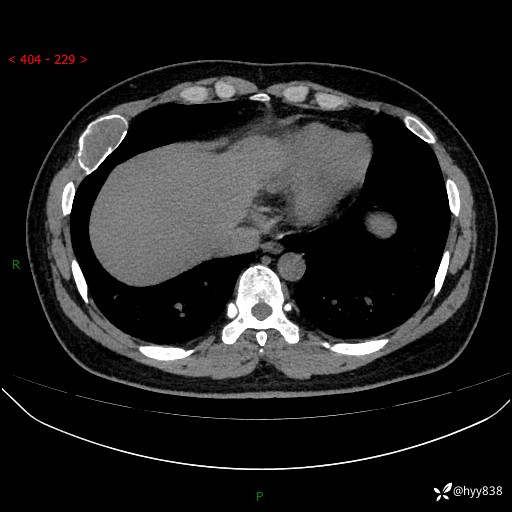

胸部CT平扫